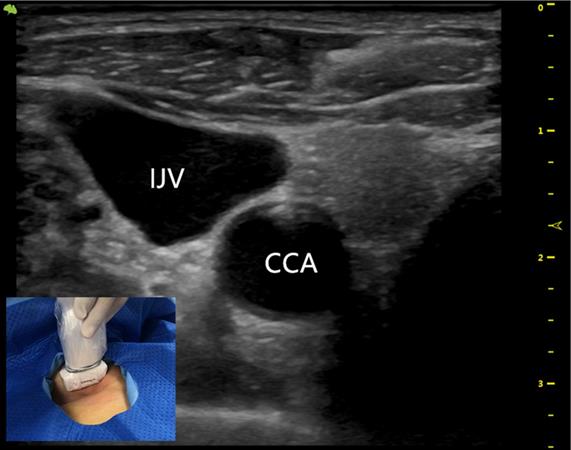

An artificial pocket of the appropriate size was created on the upper part of the chest wall, just enough to contain the port. A tunnel needle crossed over the supraclavicular region to connect the catheter and port in the pocket, and its tip was adjusted to the junction of the superior vena cava and the right atrium under fluoroscopy (Figures 3 and 4). Blood infusion and withdrawal were tested again to ensure that the infusion port functioned normally after the incision was closed.

Figure 3

A totally implantable venous access port (TIVAP) is implanted via the right BCV approach, crossing over the right clavicle. The port is located on the right chest wall, and the tip of the catheter (white arrow) is located at the junction of the superior vena cava and the right atrium.